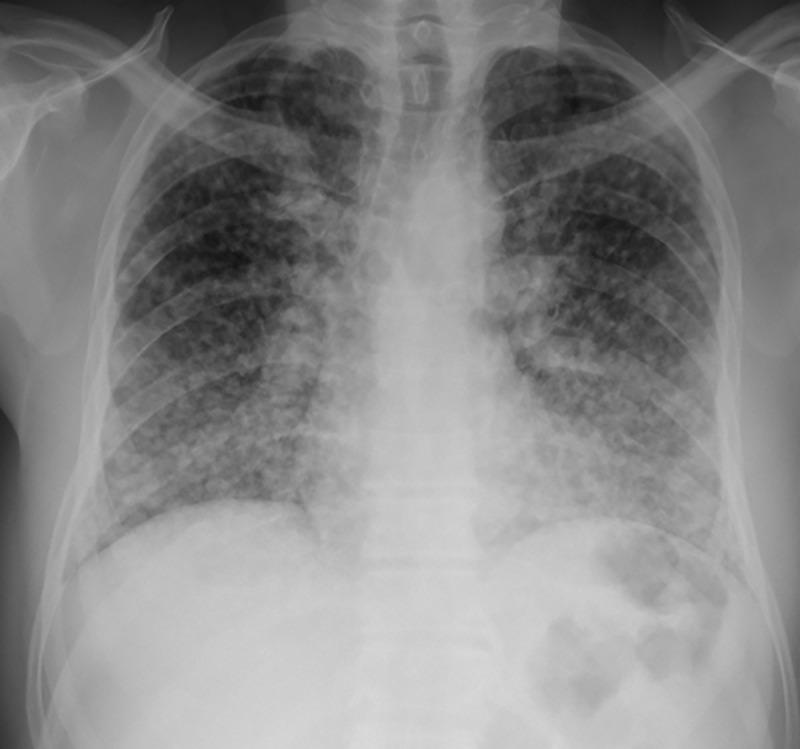

Radiological features of chronic pulmonary histoplasmosis: Easily mistaken for tuberculosis.

Histoplasma capsulatum var capsulatum is an endemic respiratory pathogen presenting in various forms including miliary histoplasmosis, acute and chronic pulmonary histoplasmosis, and acute or subacute disseminated disease. The differential diagnosis of chronic pulmonary histoplasmosis (CPH) is broad, encompassing bacterial, fungal and malignant aetiologies. PubMed was searched for relevant articles on the radiological characteristics of CPH and the most common differential diagnoses of tuberculosis and chronic pulmonary aspergillosis. The Fleischner Society Glossary of Terms for Thoracic Imaging was used to analyze the features. The contribution of culture, antibody and antigen and PCR to the diagnosis of CPH is summarized. Cavitation and pulmonary nodules are the most common features of CPH. Pleural effusion, pleural thickening, intrathoracic lymphadenopathy and bronchiectasis are not characteristic of CPH; uncommonly CPH can be complicated by an aspergilloma. Data on the radiologic features of CPH are derived primarily from the USA, Brazil, and China. CPH can be diagnosed by respiratory fungal culture (using extended culture times) or Histoplasma PCR (although data are scarce) and serum Histoplasma antigen and antibody. Data on bronchoscopy sampling for antigen are lacking. In patients with pulmonary cavitation without a confirmed diagnosis of tuberculosis or aspergillosis should be evaluated for CPH.